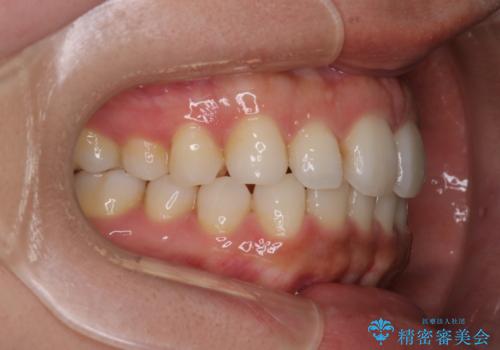

【インビザライン】前歯の後戻りを再矯正

- 前歯が出ていることを主訴に来院されました。検査の結果、口元が標準より出ているわけではなかったため今回はIPRと拡大をし、非抜歯で治療を行いました。

非抜歯でも歯軸の向きを改善したことで前歯が下がり、出っ歯に見えてしまうという主訴が改善しました。